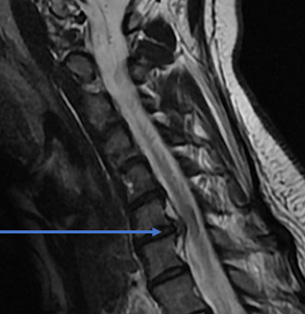

32 year old female comes with right arm pain that radiates all the way down to her fingers. We tried therapy, injections, oral pain medicine, and time. Because of the pain, a MRI showed a herniated disc in her neck on the right side (arrow). The left image is a side view and the right images is a cross section view.

She underwent a minimally invasive anterior cervical discectomy and fusion after removing the herniated disc. A MRI shows resolution of the herniated disc.